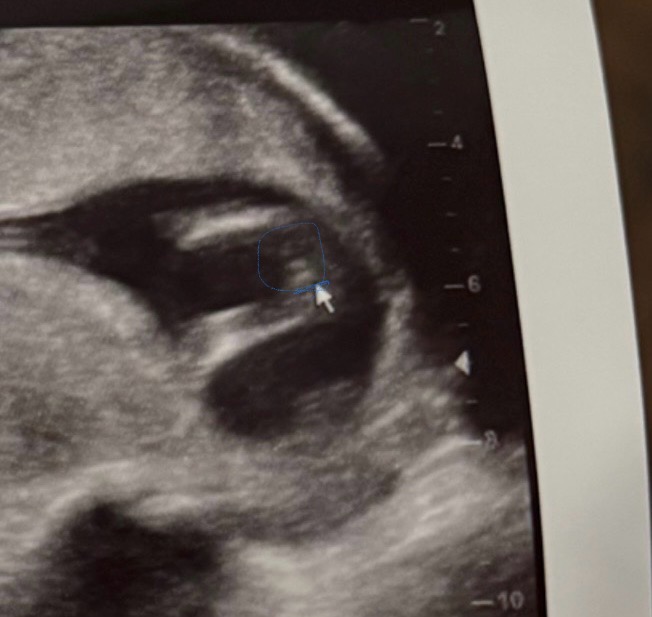

سونار 13 اسبوع و1 ذكر ولا انثى

سويت سونار 13 اسبوع و1 ذكر ام انثى؟ الدكتوره عطتني احتمال انها انثى

من واقع الصورة غالبا انثي 0 2025-12-25T23:41:40+00:00

من واقع الصورة غالبا انثي